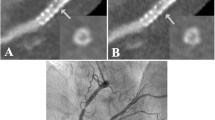

In 3/44 stents, both readers described image quality as non-diagnostic, whereas reader 2 noted a fourth stent to have non-diagnostic image quality. The overall subjective image quality of the stent lumen was rated as good to excellent by both readers (median score, 1 [IQR, 1–2.3] vs. median score, 2 [IQR, 1–2.3]; p = 0.38). An overall blooming estimate of 37.9 ± 9.6% (reader 1) and 40.1 ± 8.9% (reader 2) was observed (p = 0.03). Stents noticeably affected CT attenuation within the vessel lumen, as a median ∆HUin-stent of + 77 HU [IQR, 36–106], according to reader 1, and a median ∆HUin-stent of + 18 HU [IQR − 1 to 100], according to reader 2, were registered (p = 0.02). Detailed metrics of subjective and objective image quality are provided in Table 2. Imaging examples for patent stents are given in Figs. 3, 4 and 5 provides an example demonstrating in-stent stenosis.

Ultra-high-resolution photon-counting detector CT angiography in a 72-year-old female with severe aortic valve stenosis and a history of coronary stenting. A Three-dimensional cinematic reformation illustrating the stent in the left circumflex coronary artery (arrowheads). B Curved multiplanar reformation of the proximal left circumflex coronary artery reveals an intraluminal hypoattenuation (arrowhead), suggesting severe stenosis or complete obstruction of the in-stent lumen. C Invasive angiography (RAO 20°, CAU 10°) corroborates the obstruction of the in-stent lumen (arrowheads). Notably, the vessel’s distal part is perfused retrogradely through collateral channels (star)